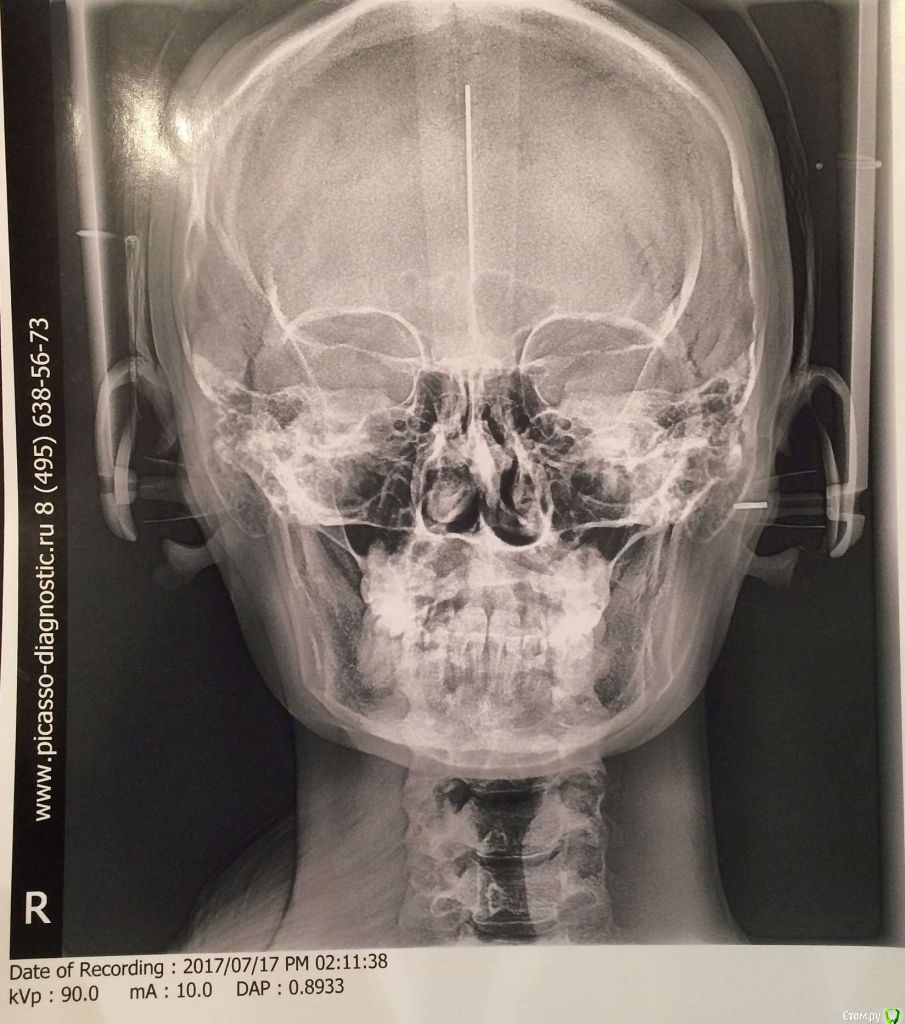

Добрый день! Очень прошу помочь с выбором врача или рекомендаций по лечению. С 2010 по 2012 год я носила брекеты (зубы были ровные, но с левой стороны верхня челюсть полностью перекрывала нижние, не было контактов, происходило стачивание). Затем с 2012 по 2016 год мне пытались исправить зубы нижней челюсти, я носила разные каппы, пластинки, то есть зубы все это время не фиксировали в определенном положении. Затем наконец в 2016-2017 году я относила полгода корректирующую каппу, которая более-менее выровняла мне нижний ряд (там была скученность). Все это время пломбы на жевательных зубах мне не меняли, они очень сильно сточились, и мне рекомендовали их заменить. Но как раз в это время у меня заболел сустав с правой стороны (на фото он соответственно слева, где и наблюдается ассиметрия). Я стала ходить по ортодонтам-ортопедам, одни говорили, что у меня все супер с прикусом, другие говорили, что клыки не под тем углом и надо снова ставить брекеты. Устав от хождений, я обратилась за диагностикой в небезызвестный центр междисдисплинарной стоматологии. Сделала там полную диагностику, по результатам которой мне предложили либо исправить брекетами клыки и поднять прикус керамическими вкладками, либо без брекетов, но тогда ставить на клыки также вкладки. Эта процедура проводится аж в три этапа и стоит как крыло самолета. Я прилагаю результаты моей диагностики. Обратилась за консультацией к другому ортопеду, который заверил, что можно обойтись временными и затем керамическими вкладками. Но помимо прикуса меня волнует ассиметрия улыбки, которая появилась в последнее время. Во-первых, я вижу невооруженным глазом, что зубы с правой стороны по высоте короче, чем с левой, то есть они меньше закрывают нижние зубы, чем с противоположной стороны, это же видно и на фото. Во-вторых, справа уголок губы при улыбке опускается как бы к низу, в отличе от левой стороны, где он идет ровно. В-третьих, с этой же правой стороны при улыбке мыщца начинается дергаться... Сейчас я уже запуталась, к какому врачу мне обращаться с данной проблемой: к ортодонту, к ортопеду, либо это гипертонус мыщц (хотя в закрытом состоянии эта ассиметрия не так заметна) Заранее благодарю за рекомендации.

Вам необходим врач-ортокраниодонт. Пытаться найти решение проблемы только на уровне зубов будет крайне трудно, да и бесполезно. Это сравнимо с симптоматическим лечением, когда идёт борьба только с симптомами заболевания, но никак не влияя на главную причину. Природа Ваших проблем (ДВНЧС, асимметрия) кроется в черепе, а точнее, в имеющимся его искажении